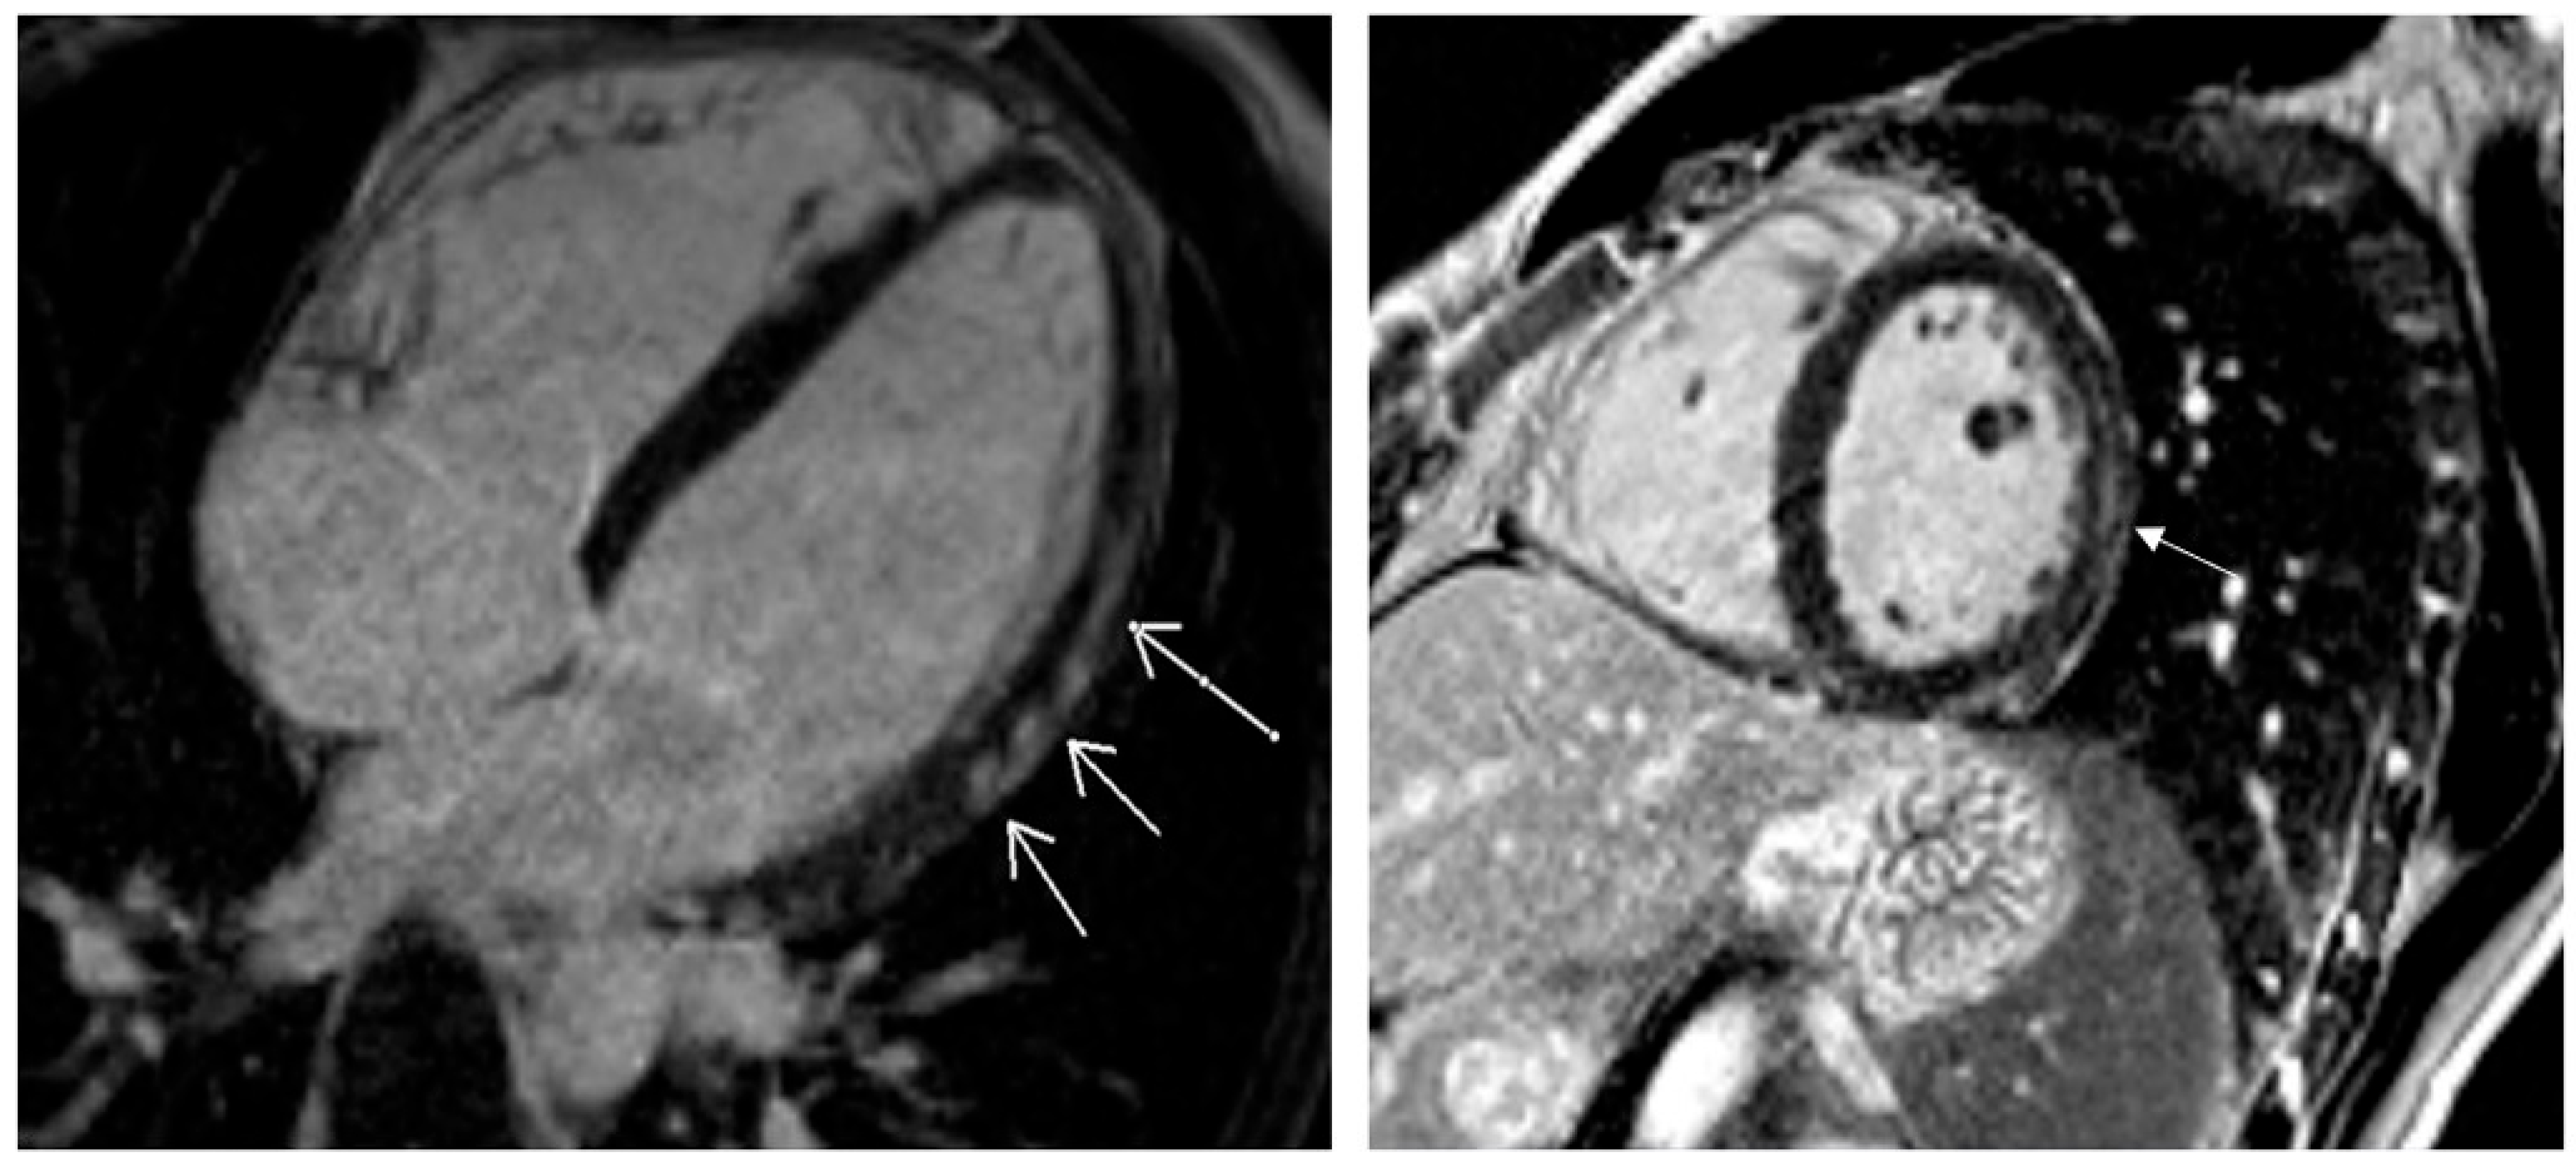

| T1 native, ms (mean ± SD) | 1035.94 ± 111.43 |

| T1 native increase, n (%) | 14 (21.0) |

| T1 post-contrast, ms (mean ± SD) | 440.81 ± 99.55 |

| T1 post-contrast increase, n (%) | 13 (19.4) |

| T2 native, ms (mean ± SD) | 45.21 ± 3.05 |

| T2 post-contrast increase, n (%) | 15 (22.4) |

| LGE positive, n (%) | 29 (43.3) |

| LGE in ≥3 segments, n (%) | 25 (37.3) |

| LGE layers, n (%) | |

| epi | 11 (37.9) |

| epi or mid | 12 (41.4) |

| mid | 6 (20.7) |

| Total abnormal, n (%) | 39 (58.2) |

| LGE positive in T1 native increase patients (%) | 50.0 |

| LGE positive in T1 post-contrast increase patients (%) | 30.8 |

| LGE positive in T2 native increase patients (%) | 70.0 |

| Pericarditis, n (%) | 8 (12.5) |